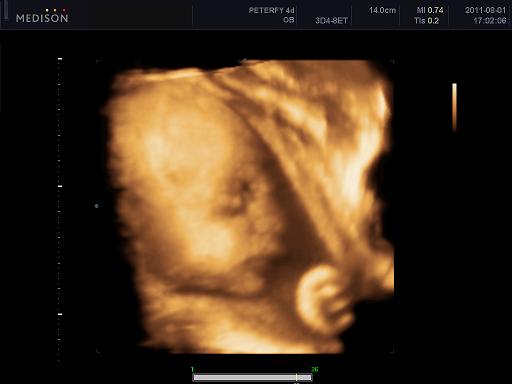

Velünk minden oké szerencsére, dundisodok én is, a baba is tök szuperül van ééééés tegnap voltunk végre 4D-n, annyira nagy élmény volt lányok!!!! Nem is gondoltam h ez ennyire jó dolgo, azzal együtt, hogy Alma nagyon bújócskázott, végig az arcát simizte meg takargatta, csak néha kaptunk egy kis mosolyt de imádom, végtelenül nagy boldogság ez a kis csöppség!!!!! :)

1250 grammos és kis ficánka, meg a szonográfus csaj is mondta hogy mennyire kis cserfes már most! :D

Kép